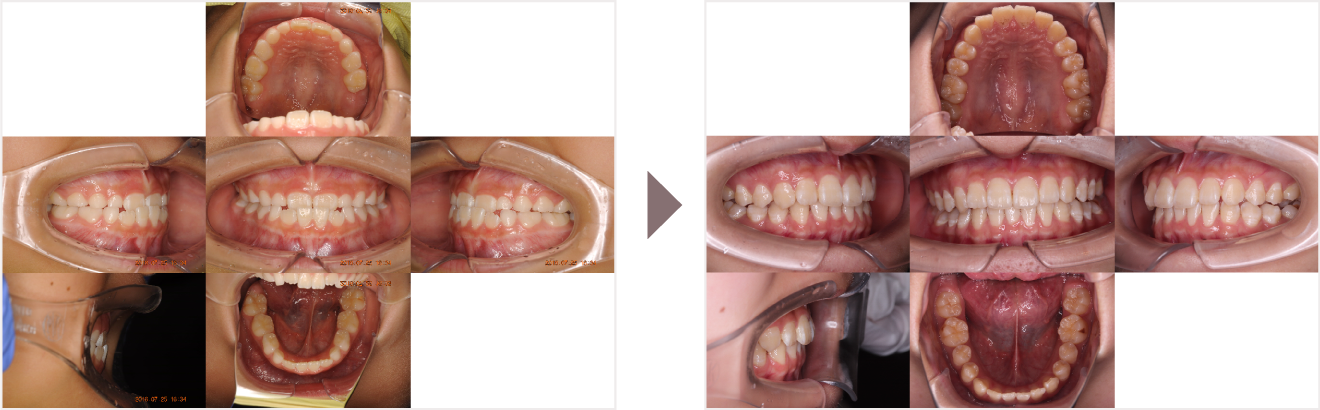

症例叢生

性別

期間6年5ヶ月

治療内容N-Bimler装置、Neo-Capを使用して治療

治療における

副作用・リスク

装着しないと効果は出ません

金額ビムラー装置:550,000円

ネオキャップ:4本

合計:572,000円